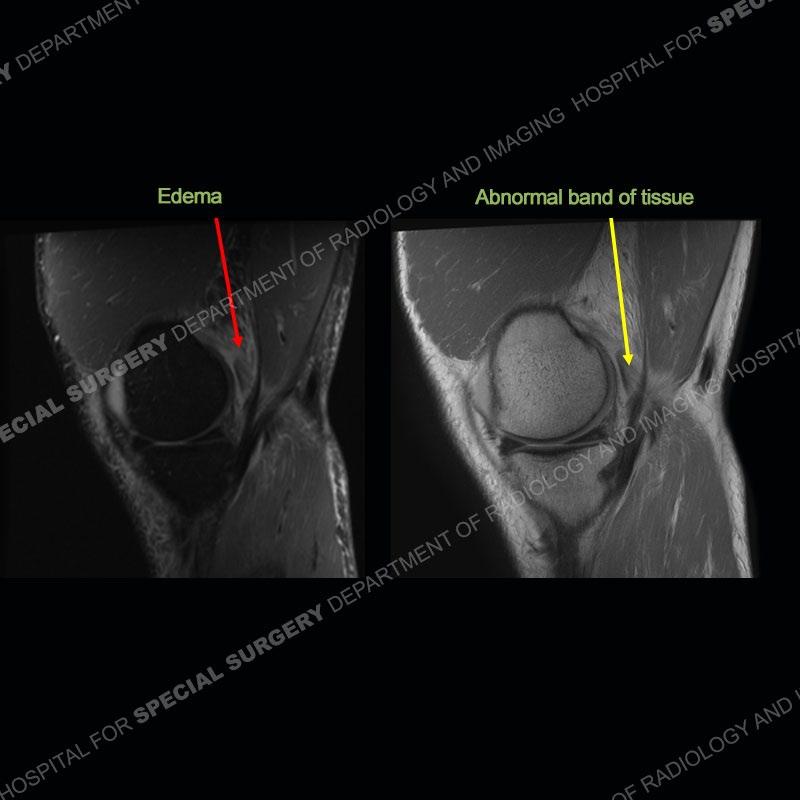

Findings

The radiographs show degenerative change of the medial compartment and a varus knee, but they are not germane to this case. No acute bony injury is present. The MRI shows edema of the posterior medial knee/soft tissue and a focal area of a partially disrupted low signal structure. The details are kept at a minimum in the findings of this case on purpose.

Diagnosis: Partial Disruption Medial Head Gastrocnemius (MHG)

The findings were kept purposefully vague as identifying the structures early on takes away a lot of the diagnosis. An uncommon entity and one of which we do not see a lot. Enthesopathic changes and tendinosis are seen as are distal MHG injuries, but proximal tears are rarely present. This case highlights a number of points. One, it almost always comes down to anatomy. Perhaps not a structure we normally spend too much time on, except save for diagnosing a Baker’s cyst, but knowing where this structure and all structures exist in all three planes is imperative. Second, when you think you are making a “call” or finding that you have never made before, step back and think is this just the abnormal presentation of a common pathology. That situation arises much more frequently. Third, if you look at it once, twice, and probably a third time and are confident in your odd or very rare diagnosis, stick to your guns. Especially, when it comes down to anatomic structures, the proof will be in the images.

Fourth, use all imaging planes and different pulse sequences to make your diagnosis. The edema highlighted in this case can be seen as the obscuration of fat on the PD images but is much easier to perceive as the high signal on the IR pulse sequences. The actual disruption of the MHG myotendinous junction is only able to be seen on the axial images. On the sagittal and coronal images, we get a sense something is wrong but hard to be exact. Lastly, when you look at a study and something just seems off (as I would say the sagittal and coronal images do with that dark band of tissue posteriorly), listen to yourself and go through the study slowly and meticulously. Most of the time you will find you were right, and something indeed is present.